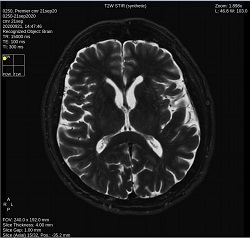

- By default, a 6-viewport display is launched with 6 unique MAGiC images.

Click T2W STIR to change the image contrast to synthetic T2W STIR-weighted.